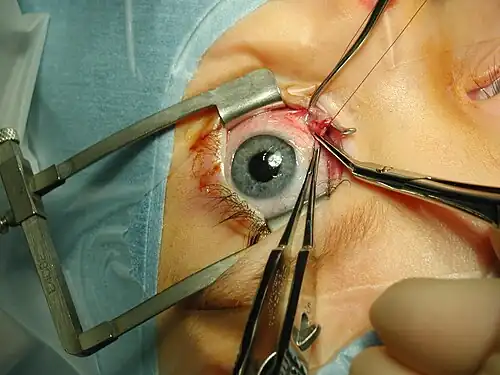

Medicine has been practiced since prehistoric times, and for most of this time it was an art (an area of creativity and skill), frequently having connections to the religious and philosophical beliefs of local culture. For example, a medicine man would apply herbs and say prayers for healing, or an ancient philosopher and physician would apply bloodletting according to the theories of humorism. In recent centuries, since the advent of modern science, most medicine has become a combination of art and science (both basic and applied, under the umbrella of medical science). For example, while stitching technique for sutures is an art learned through practice, knowledge of what happens at the cellular and molecular level in the tissues being stitched arises through science.

Selected image –

General images –